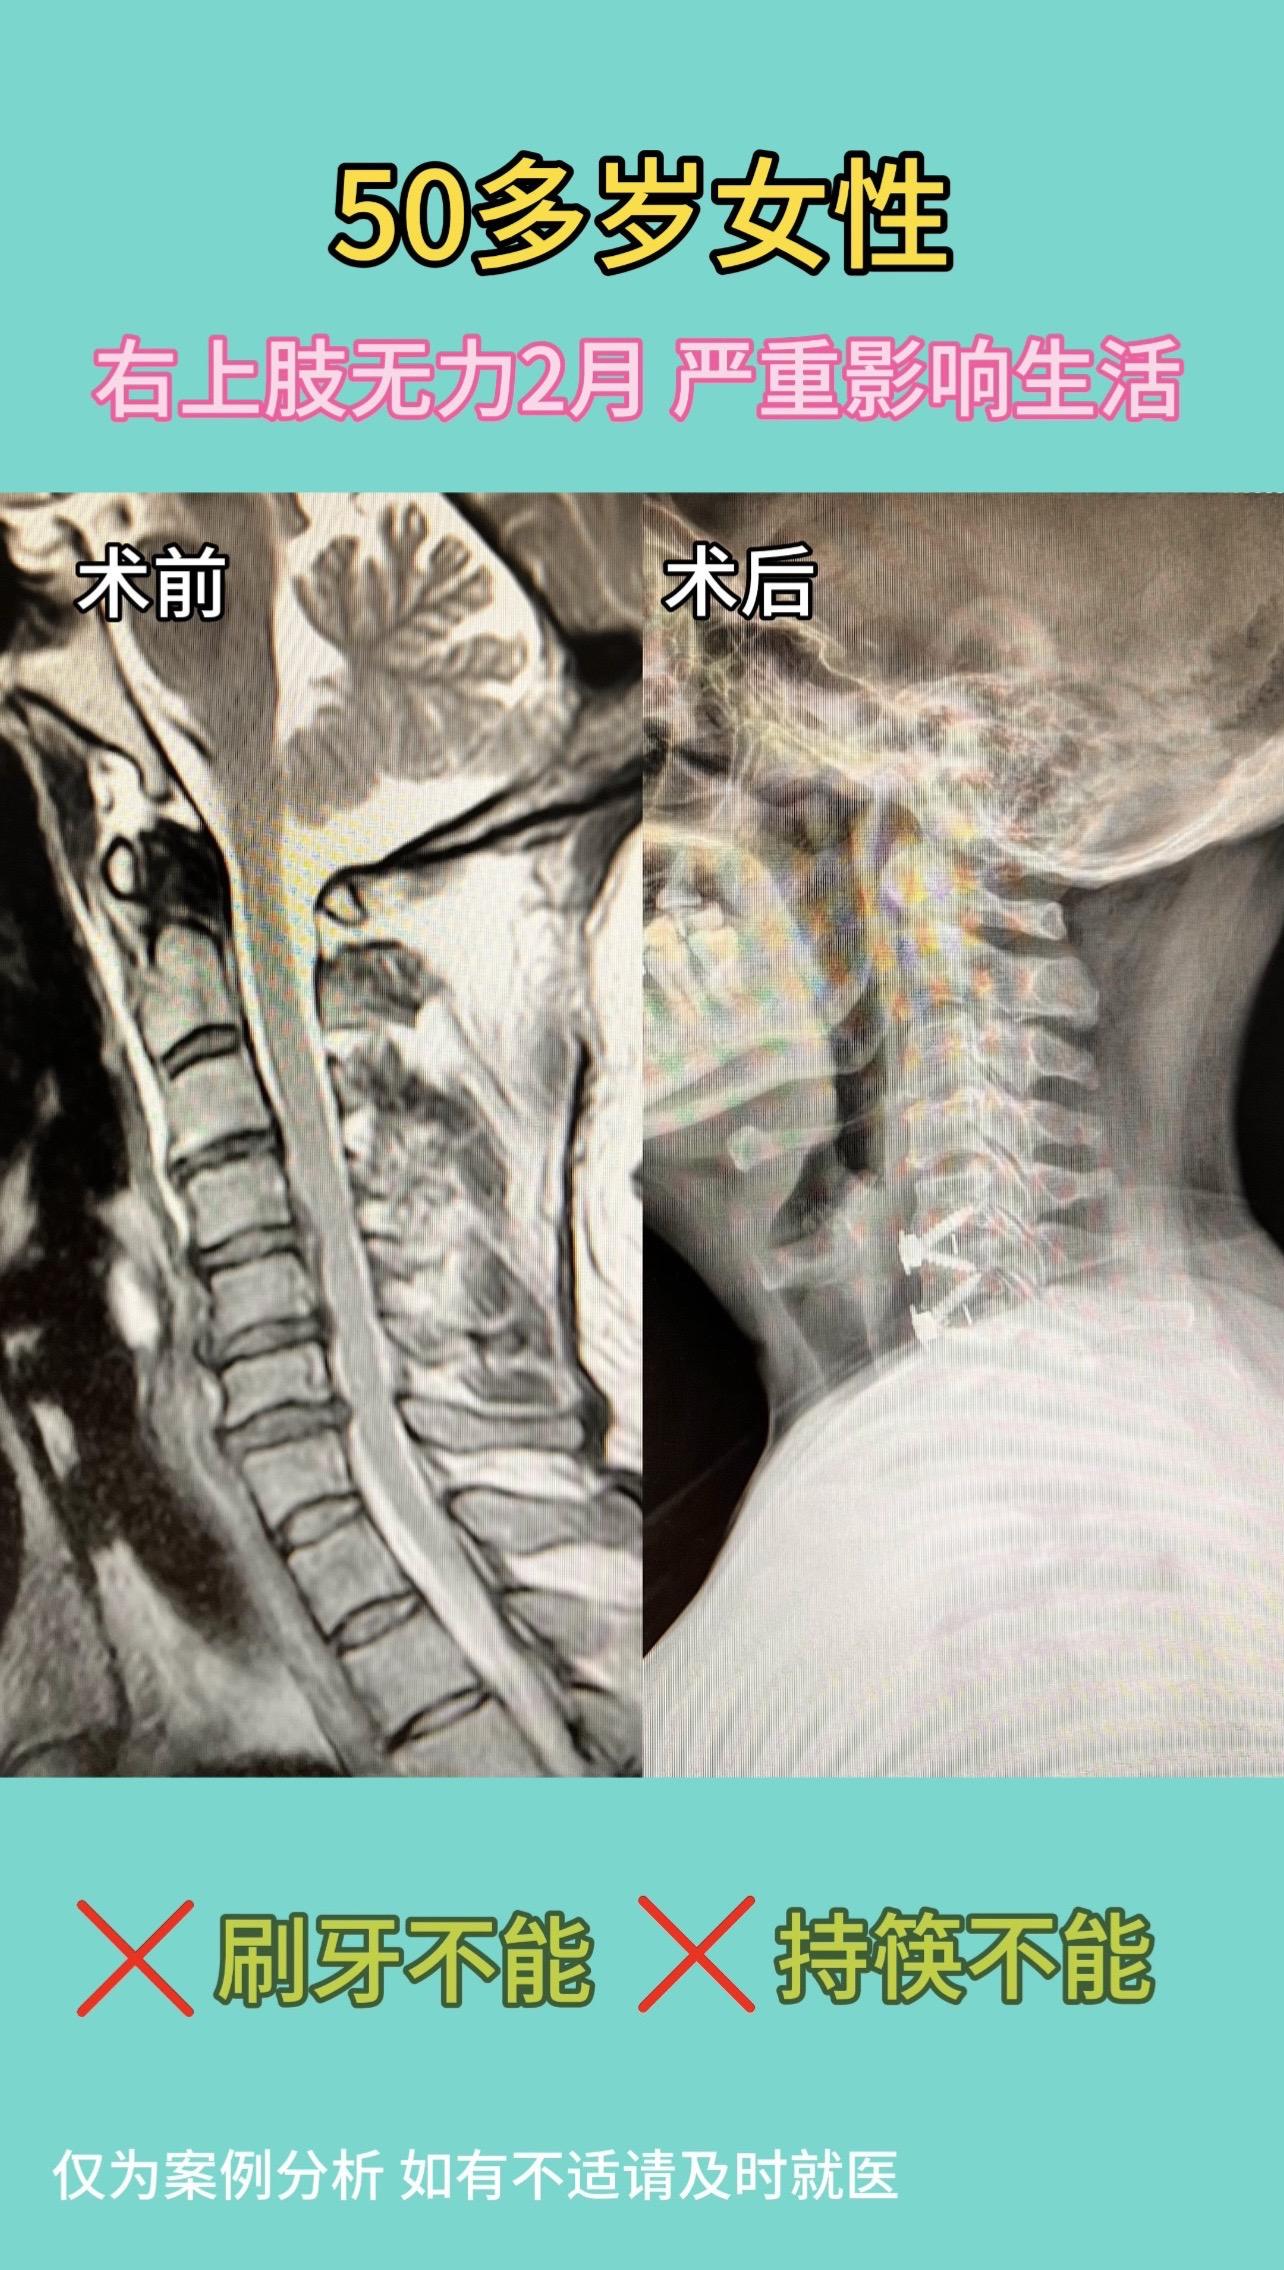

50多岁女性,右上肢无力2月,刷牙不能,持筷不能。严重影响生活。术后1...